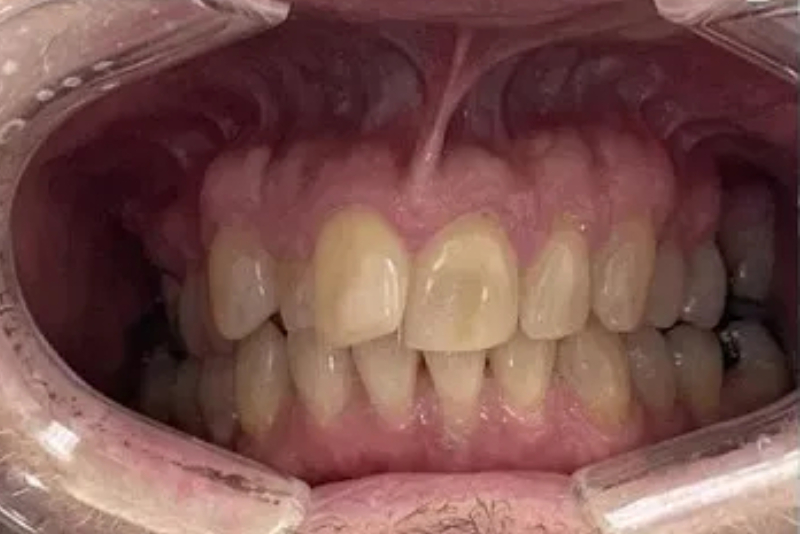

Before

After

A patient came in with severely loose upper teeth and bone loss, affecting daily functions like eating and speaking. Dr. Singh’s team performed a same-day full-arch implant procedure—extracting the remaining teeth, placing six implants, and providing fixed temporary teeth all in one day. The treatment restored both function and confidence, giving the patient an immediate, life-changing improvement.